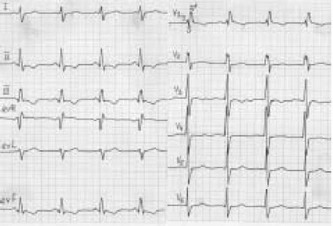

• ДМПП является структурным дефектом и за исключением вторичного ДМПП не подвергается спонтанному закрытию и, следовательно, требует хирургического закрытия. Вторичные дефекты размером 6 мм и менее могут спонтанно закрываться в первые годы: жизни, однако скорость закрытия происходит медленнее, чем при типичных маленьких мышечных дефектах межжелудочковой перегородки. Новорожденные с ДМПП и застойной сердечной недостаточностью, а также дети с большим ДМПП, у которых возникла сердечная недостаточность, должны получать лечение, включающее диуретики, дигоксин и препараты, уменьшающие постнагрузку. Аритмия в сочетании с ДМПП редко наблюдается у детей, но появляется с возрастом. Мерцательная аритмия у больных с ДМПП возникает после 40 лет. Аритмия обусловлена перерастяжением предсердия и в ряде случаев может потребовать антиаритмической терапии до проведения хирургической коррекции. Рис. 17. Вторичный дефект межпредсердной перегородки: признаки

Рис. 17.

Вторичный дефект межпредсердной перегородки: признаки гипертрофии миокарда правого желудочка, неполная блокада правой ножки пучка Гиса.